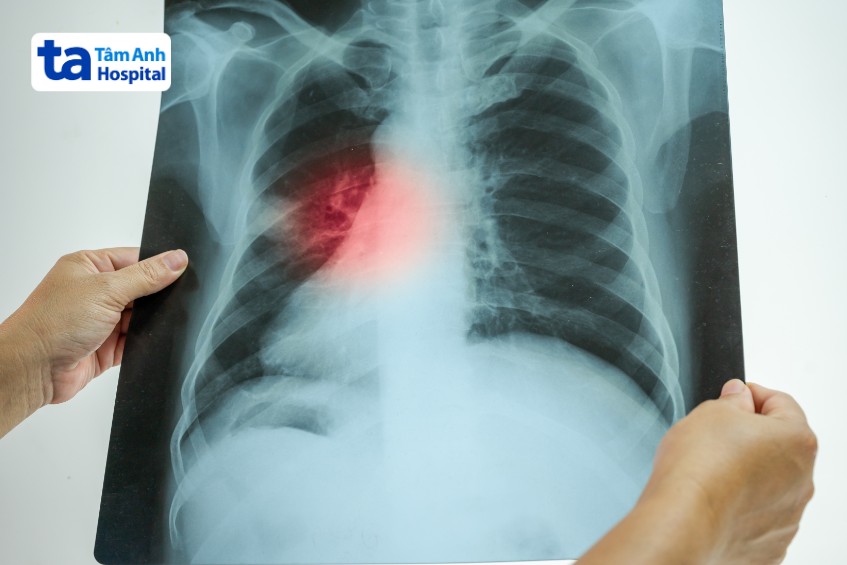

Chụp x-quang phổi là chẩn đoán cận lâm sàng quan trọng. Mục đích nhằm giúp bác sĩ quan sát và xác định sự hiện diện của dịch phổi, vị trí tổn thương mô phổi. Ở người mắc viêm phổi cộng đồng, quan sát hình ảnh x-quang thấy có vùng mờ hoặc thâm nhiễm.